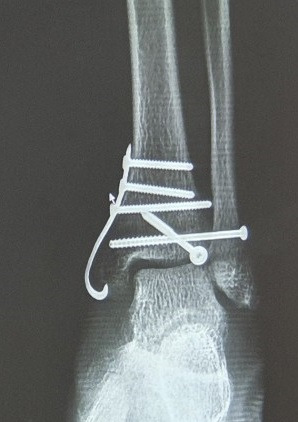

이번에도 무시했던 퇴원비 기다리다가 찾아보니 제일 많이 나오는듯.. 물론 다 이유가 있는듯. 전에. 그는 그것을 확인했다. 이 말을 듣고 또 겁이 나서 사진을 찍었다고 한다. 안전하지 않은 혼합물이 포함되어 있습니다. 이들 중 가장 큰 것은 인공 골분과 같은 것입니다. 의사선생님 말씀에 처음에 넣었다가 동의서에 싸인하고 보니 저렴한 비보험 서비스인줄 알았어요 MRI, 인조골분, 비급여약값 빼면 , 100만 원을 추가로 절약할 수 있었습니다. , 실제 비용 덕분에 정말 운이 좋았습니다. 이번 2건의 수술은 기존에 납부했던 실비를 소진한 것으로 보입니다(참고로 2016년 등록 실비입니다). 또 이번에는 배제가 커서 또 입원 신고가 들어와 모두 접수됐다. 어쨌든 내가 할 수 있고 다리 건강을 유지하는 한 그것은 낭비가 아닙니다. 건강은 무조건 중요하고 중요합니다.

삼각골절정판제거/ 삼각골절정판제거+허리통증 #삼각대골절정술 #삼각대골절정술 #삼트릭스골절정술 #삼트릭스골절정정술 #삼각절단술 … m .blog.naver.com